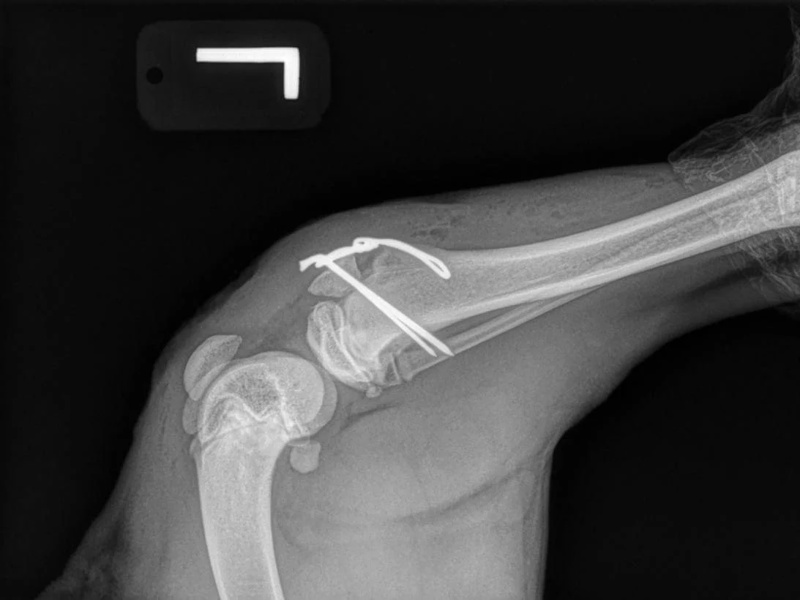

While the patient is still anesthetized, the patient is taken into radiology for post-surgery radiographs (X-rays). The radiographs are assessed to ensure the apparatus FASTak screw and toggle are appropriately positioned.

Post-op of a Hip Replacement

Shoulder Osteochondritis Dissecans (OCD) with a SynaCart Implant